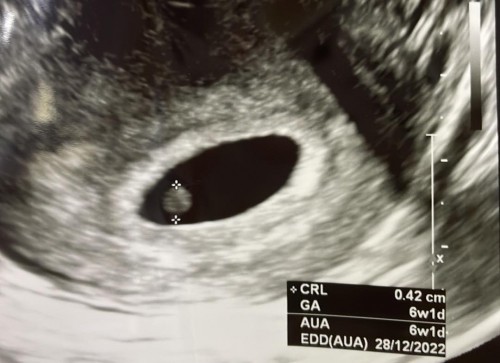

ปกติกี่วีคเห็นหัวใจน้องค่ะ แม่บ้านนี้ไปหาหมอมา แจ้งว่า 6 วีค แต่ยังไม่เจอหัวใจ หมอนัดอีกทีวันพุธที่จะถึง แต่แอบกังวลกลัวว่าน้องจะไม่อยู่ค่ะ